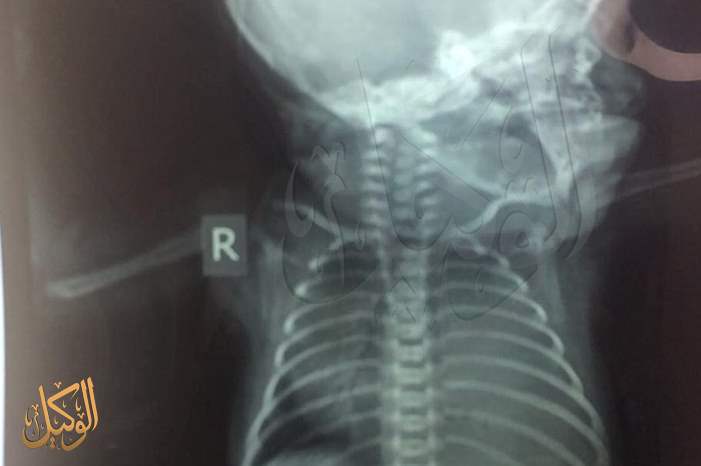

الوكيل الاخباري - بهاء سلامة - ناشد ذوو الطفل محمد أكرم حسن الذي يعاني من ضمورٍ في الرئة منذ لحظة ولادته في إحدى المستشفيات الخاصة، وزارة الصحة و المؤسسات الحكومية و الديوان الملكي العامر أن يساعدوهم في إيجاد سرير "خداج" مستشفى حكومي، لأن المبالغ اليومية التي تترتب على وجود محمد تثقل كاهل والده أكرم، الذي أشار في حديثه لموقع الوكيل الإخباري من صعوبة تأمين المبلغ الحالي لتواجد طفله في خداج المستشفى الخاص.